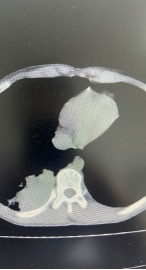

通常医生会采用肺部CT,来寻找“病灶”的大致方位。但若犄角旮里出现“阴影”或不明原因肺部感染,导致无法辨别“真身”时,就得派出“侦察兵”——支气管镜了。通俗的说,支气管镜就是把镜子伸到气管或支气管里,观察气管和支气管的病变,并根据病变进行相应的检查和治疗。

一位重症肺炎儿童,在经验性针对支原体感染阿奇霉素抗感染治疗无效,经气管镜下处理,吸引出痰栓,灌洗液NGS检查提示明确为耐阿奇霉素支原体肺炎,调整治疗后迅速病愈出院。